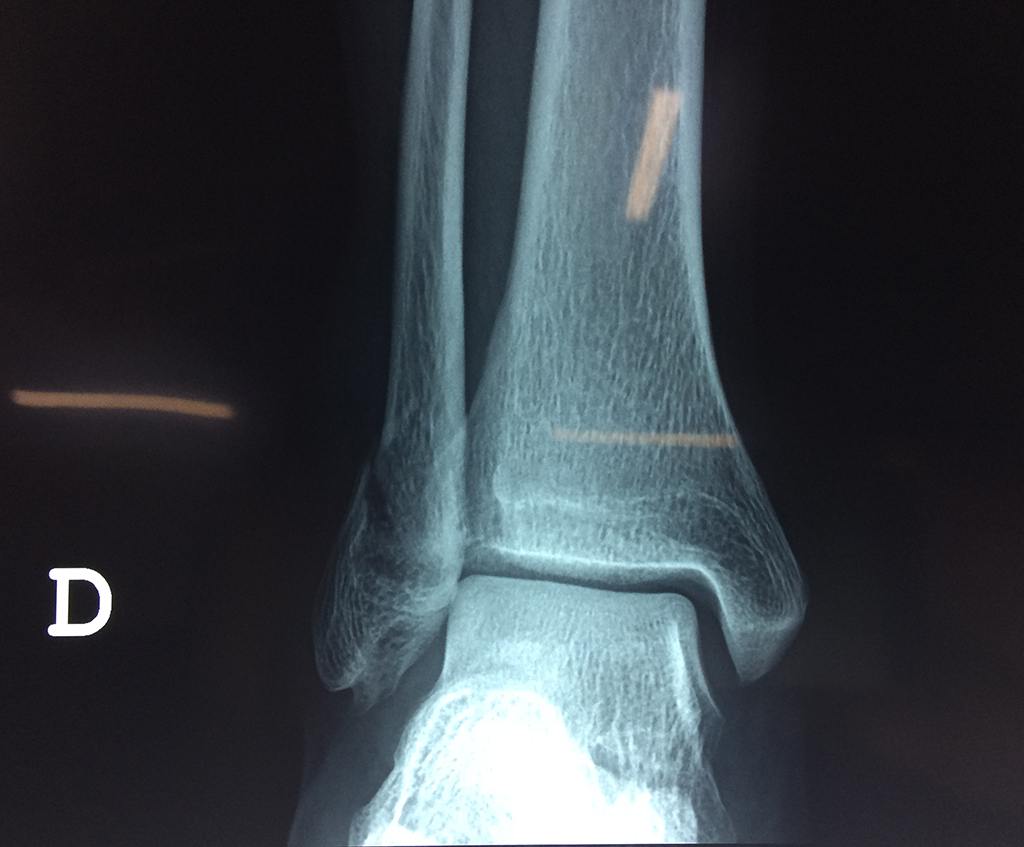

Algunas fracturas de tobillo pueden requerir cirugía si:

- Los extremos de los huesos están desalineados entre sí (desplazados).

- El médico cree que sus huesos probablemente no sanen apropiadamente sin cirugía.

- El médico considera que la cirugía puede permitirle una recuperación más rápida y confiable.

Cuando se necesita cirugía, es probable que esta implique el uso de clavijas de metal, tornillos o placas para sostener los huesos en su lugar mientras la fractura se consolida. Los elementos de soporte pueden ser temporales o permanentes.